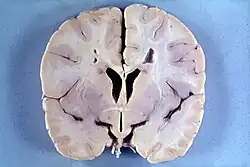

Macrocephaly from hydrocephalus

Macrocephaly from megalencephaly